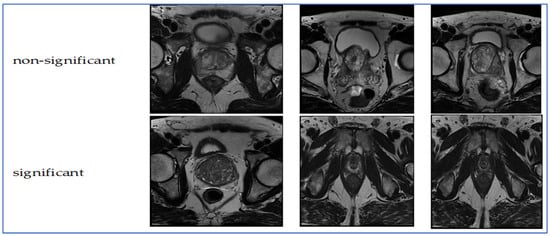

A Multi-Stage Hybrid Learning Model with Advanced Feature Fusion for Enhanced Prostate Cancer Classification

by Sameh Abd El-Ghany and A. A. Abd El-Aziz

Background: Cancer poses a significant health risk to humans, with prostate cancer (PCa) being the second most common and deadly form among men, following lung cancer. Each year, it affects over a million individuals and presents substantial diagnostic challenges due to variations [...] Read more.

Background: Cancer poses a significant health risk to humans, with prostate cancer (PCa) being the second most common and deadly form among men, following lung cancer. Each year, it affects over a million individuals and presents substantial diagnostic challenges due to variations in tissue appearance and imaging quality. In recent decades, various techniques utilizing Magnetic Resonance Imaging (MRI) have been developed for identifying and classifying PCa. Accurate classification in MRI typically requires the integration of complementary feature types, such as deep semantic representations from Convolutional Neural Networks (CNNs) and handcrafted descriptors like Histogram of Oriented Gradients (HOG). Therefore, a more robust and discriminative feature integration strategy is crucial for enhancing computer-aided diagnosis performance. Objectives: This study aims to develop a multi-stage hybrid learning model that combines deep and handcrafted features, investigates various feature reduction and classification techniques, and improves diagnostic accuracy for prostate cancer using magnetic resonance imaging. Methods: The proposed framework integrates deep features extracted from convolutional architectures with handcrafted texture descriptors to capture both semantic and structural information. Multiple dimensionality reduction methods, including singular value decomposition (SVD), were evaluated to optimize the fused feature space. Several machine learning (ML) classifiers were benchmarked to identify the most effective diagnostic configuration. The overall framework was validated using k-fold cross-validation to ensure reliability and minimize evaluation bias. Results: Experimental results on the Transverse Plane Prostate (TPP) dataset for binary classification tasks showed that the hybrid model significantly outperformed individual deep or handcrafted approaches, achieving superior accuracy of 99.74%, specificity of 99.87%, precision of 99.87%, sensitivity of 99.61%, and F1-score of 99.74%. Conclusions: By combining complementary feature extraction, dimensionality reduction, and optimized classification, the proposed model offers a reliable and generalizable solution for prostate cancer diagnosis and demonstrates strong potential for integration into intelligent clinical decision-support systems. Full article

Show Figures

Figure 1